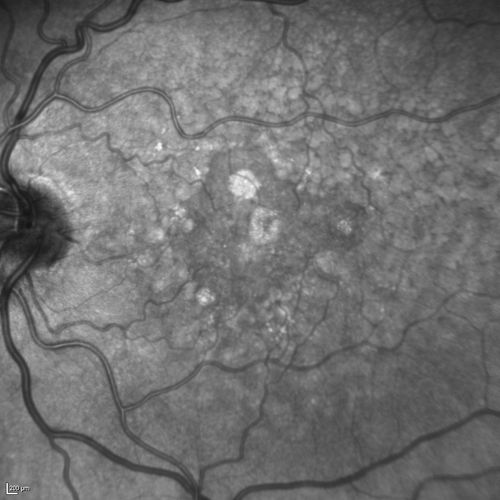

Dry AMD - Confluent Drusen Sparing Center of Macula which has Atrophy

65 year old woman, VA 20/40 OD; 20/80 OS. The center of the macula has few or no drusen with predominantly non-geographic atrophy